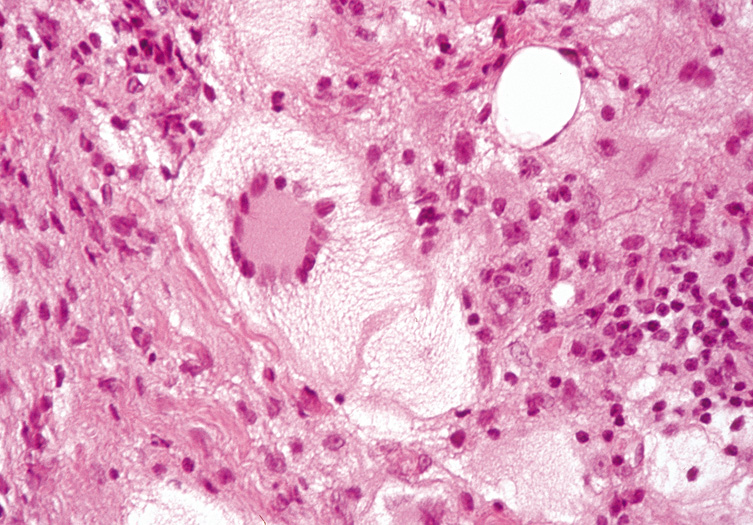

An external hordeolum (stye) (Fig. 4) results from an acute purulent inflammation of the superficial sweat and sebaceous glands or hair follicles of the eyelids, while an internal hordeolum occurs in the meibomian glands within the tarsal plates of the lids. They are characterized histologically by dense inflammation containing neutrophils and foreign body multinucleated giant cells around intact or ruptured appendegeal structures. A chalazion is chronic inflammation of a meibomian gland (deep type) or zeisian sebaceous gland (superficial type) resulting in a clinically firm, painless nodule of the eyelid (Fig. 5A). Histologically, there is deep dermal or subcutaneous suppurative granulomatous inflammation containing neutrophils, plasma cells, lymphocytes, histiocytes, and giant cells in a zonal configuration around central lipid material (see Fig. 5B).

Fig. 5. Chalazion—A. Typical clinical appearance of chalazion. B. Lipogranulomatous reaction with epithelioid cells, lymphocytes, and plasma cells surrounding a central nidus of Meibomian gland secretion. Clear area in center represents lipid material dissolved out during processing of tissue. Giant cells are sometimes seen (hematoxylin and eosin stain). (Photos courtesy of William Morris, M.D.)